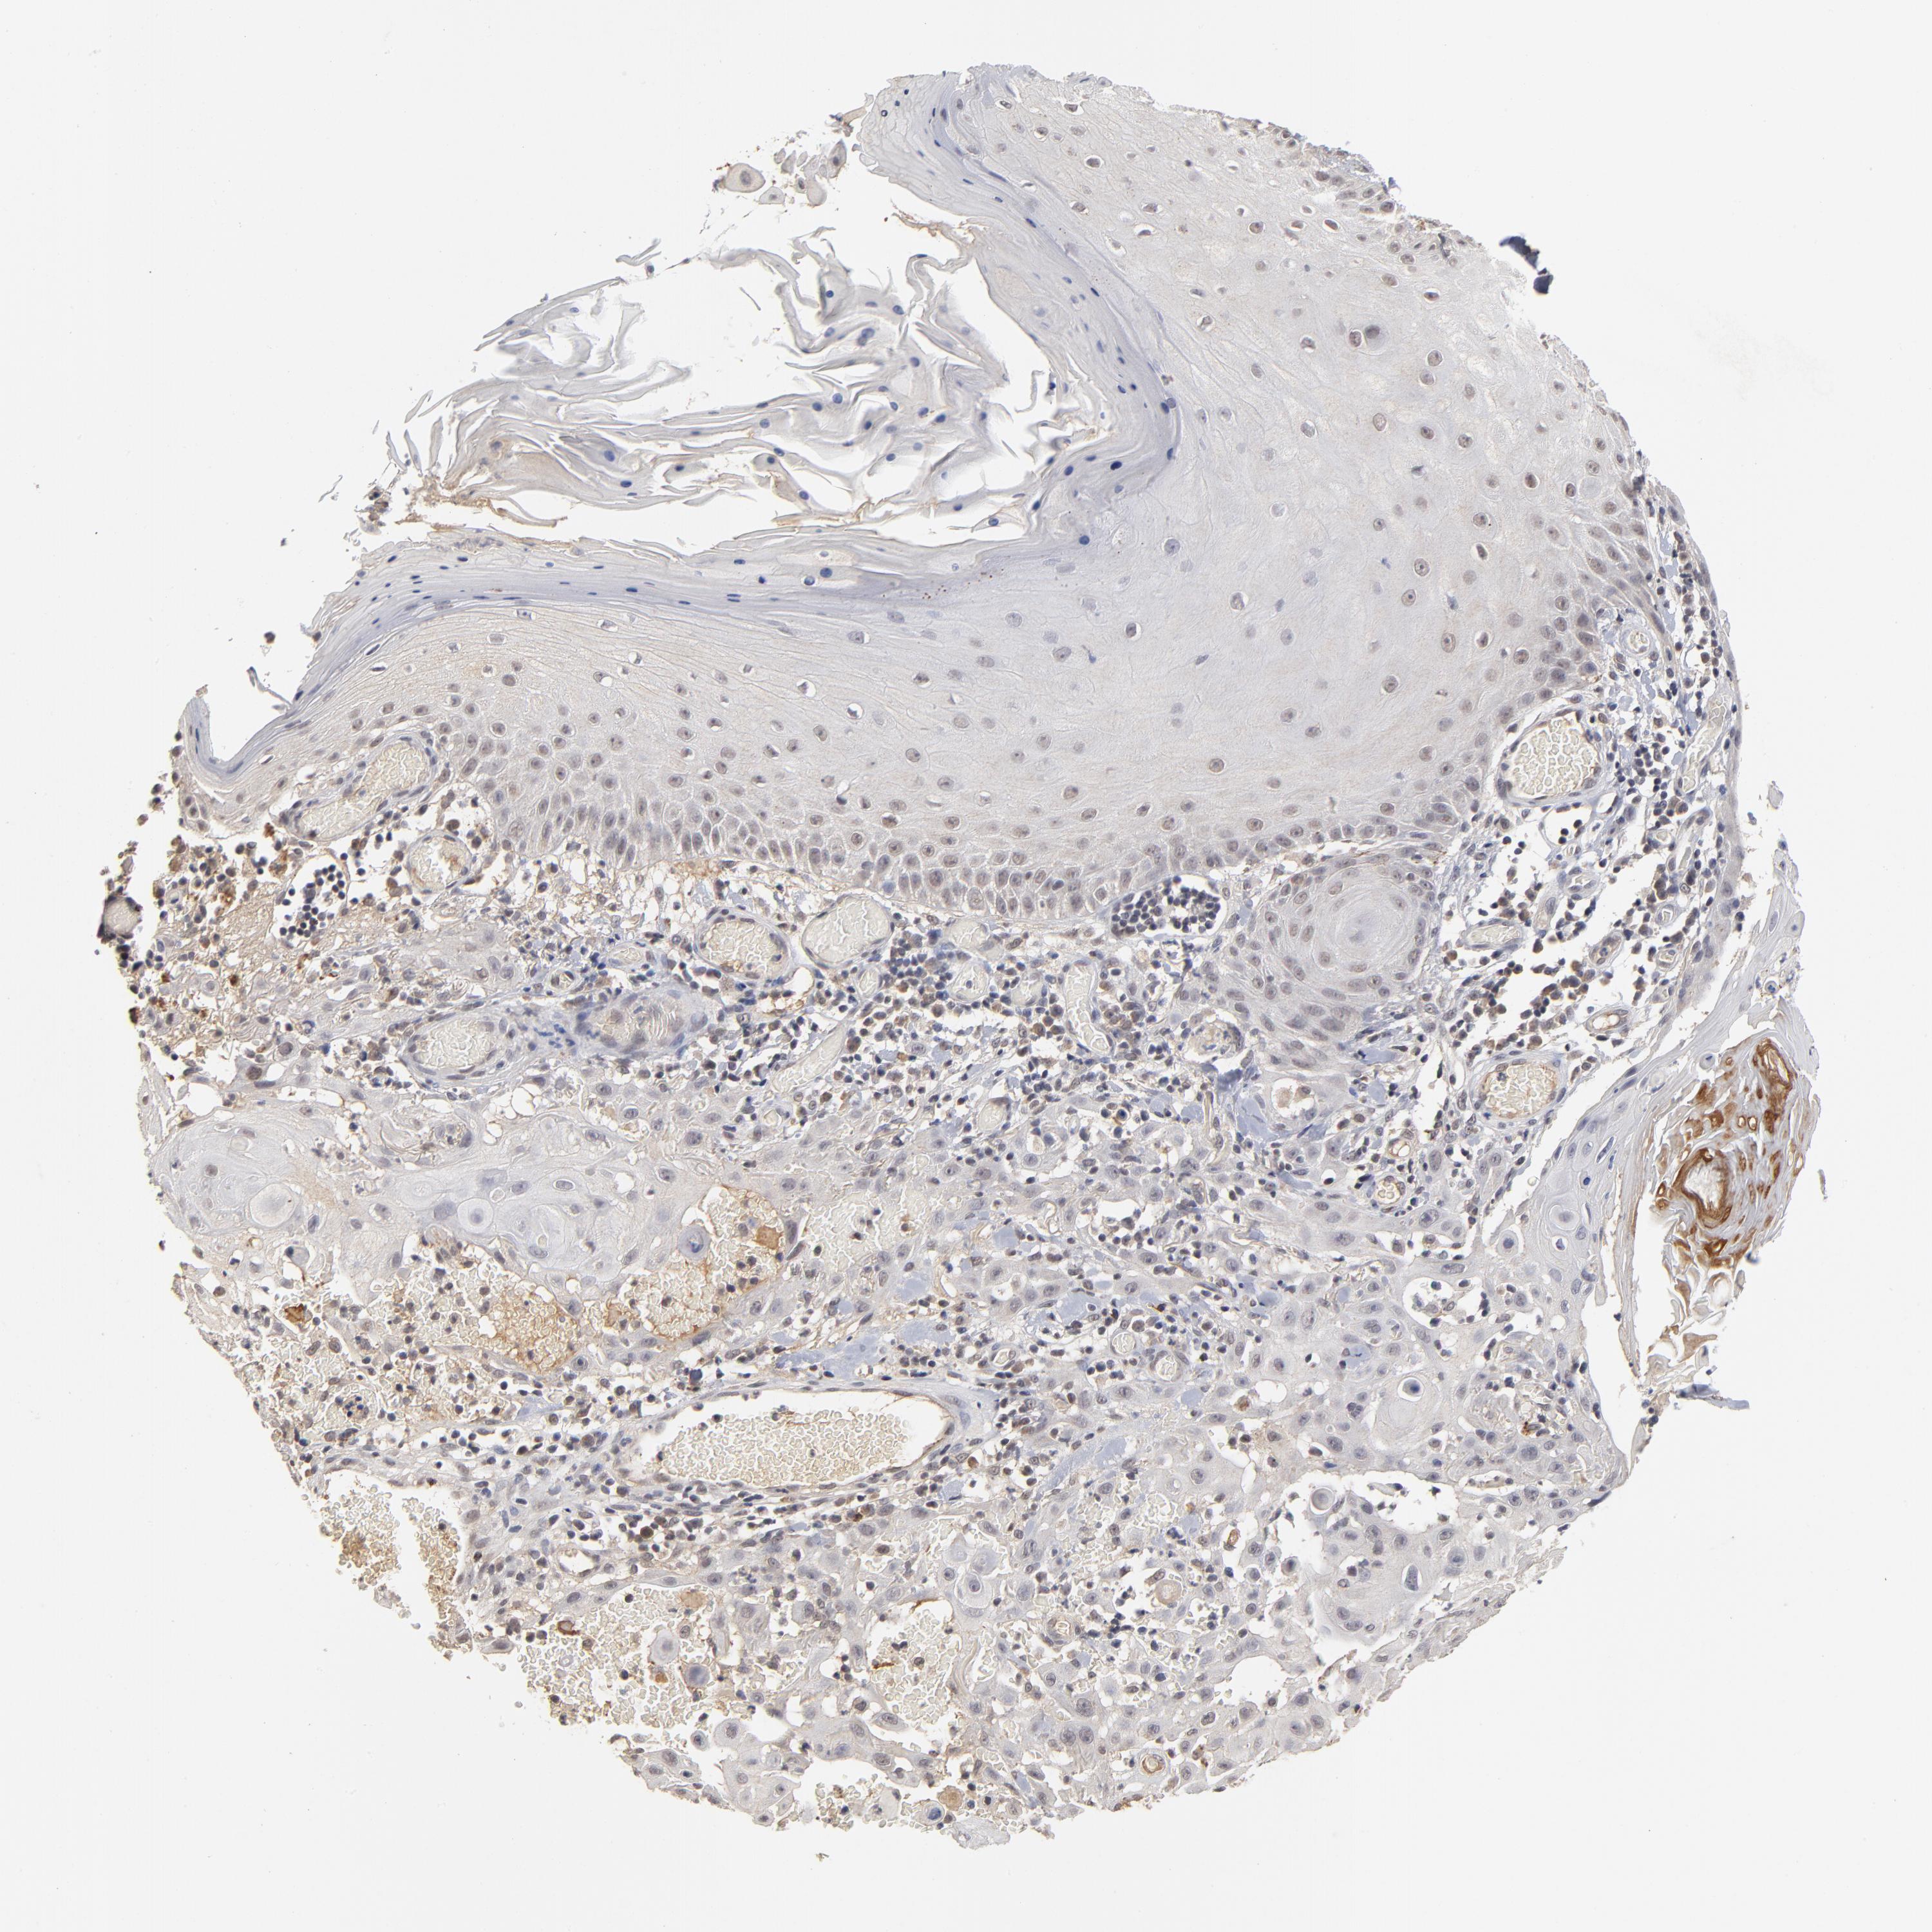

SKIN CANCER - Protein expressioni

A mouse-over function shows sample information and annotation data. Click on an image to view it in a full screen mode. Samples can be filtered based on level of antibody staining by selecting one or several of the following categories: high, medium, low and not detected. The assay and annotation is described here.

Antibody stainingi

Antibody staining in the annotated cell types in the current human tissue is reported as not detected, low, medium, or high, based on conventional immunohistochemistry profiling in selected tissues. This score is based on the combination of the staining intensity and fraction of stained cells.

Each image is clickable and will lead to virtual microscopy that enables deeper exploration of all samples and also displays staining intensity scores, fraction scores and subcellular localization as well as patient and tissue information for each sample.

Antibody HPA003293

Staining

High

Medium

Low

Not detected

Intensity

Strong

Moderate

Weak

Negative

Quantity

>75%

75%-25%

<25%

None

Location

Nuclear

Cytoplasmic/membranous

Cytoplasmic/membranous,nuclear

Squamous cell carcinoma, NOS

Basal cell carcinoma